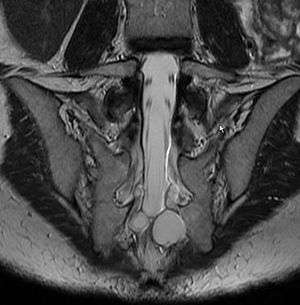

| MRI image showing a Tarlov cyst. | |

Tarlov cysts, also known as perineural cysts,[1] are type II innervated meningeal cysts, cerebrospinal-fluid-filled (CSF) sacs most frequently located in the spinal canal of the S1-to-S5 region of the spinal cord (much less often in the cervical, thoracic or lumbar spine), and can be distinguished from other meningeal cysts by their nerve-fiber-filled walls. Tarlov cysts are defined as cysts formed within the nerve-root sheath at the dorsal root ganglion.[2] Since Tarlov cysts are cysts of the spinal meninges, symptomatic Tarlov cysts by definition cause myelopathy. The etiology of these cysts is not well understood; some current theories explaining this phenomenon have not yet been tested or challenged but include increased pressure in CSF, filling of congenital cysts with one-way valves, inflammation in response to trauma and disease. They are named for neurologist Isadore Tarlov, who described them in 1938.[3]

Tarlov cysts are most commonly located in the S1 to S4/S5 region of the spinal canal, but can be found along any region of the spine. They usually form on the extradural components of sacrococcygeal nerve roots at the junction of dorsal root ganglion and posterior nerve roots and arise between the endoneurium and perineurium.[13] Occasionally, these cysts are observed in the lumbar and thoracic spine.[10] However, these cysts most commonly arise at the S2 or S3 junction of the dorsal nerve root ganglion.[7][14] The cysts are often multiple, extending around the circumference of the nerve, and can enlarge over time to compress neighboring nerve roots, to cause bone erosion.[15] The cysts may be found anterior to the sacral area and have been known to extend into the abdominal cavity. These cysts, though rare, can be found to grow large - over 3–4 centimetres (1.2–1.6 in) in size, often causing severe abdominal pain from compression on the cyst itself as well as adjoining nerves.

Two most commonly used and effective examination method for Tarlov Cysts are MRI and CT. Both CT and MRI are good imaging procedures that allow the detection of extradural spinal masses such as Tarlov cysts. Magnetic resonance neurography is an emerging imaging technology based on MRI that highlights neurologic tissue. Often cysts are under reported and under diagnosed as radiologists and neurosurgeons have been traditionally taught to ignore these cysts. Patients frequently experience difficulty in diagnosis, however this is changing as Tarlov cysts have now been recognized by NORD as a rare disease.[17]

MRI

MRI, or Magnetic Resonance Imaging, is considered the imaging study of choice in identifying Tarlov cysts. MRI provides better resolution of tissue density, absence of bone interference, multiplanar capabilities, and is noninvasive. Plain films may show bony erosion of the spinal canal or of the sacral foramina On MRI pictures, the signal is the same as the CSF one.